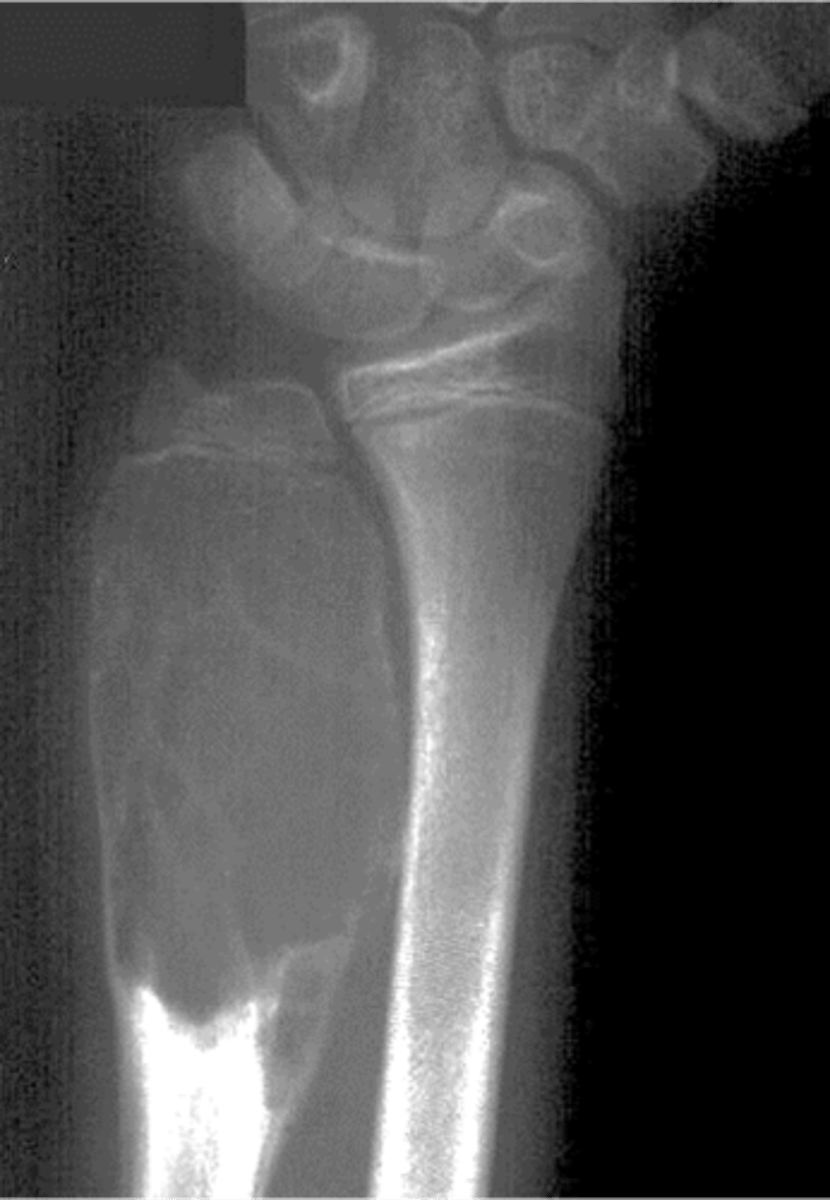

Geographic bone blister

ID radiographic feature of non-ossifying fibroma indicated by top arrow

<p>ID radiographic feature of non-ossifying fibroma indicated by top arrow</p>

Septations

ID radiographic feature of non-ossifying fibroma indicated by bottom arrow

<p>ID radiographic feature of non-ossifying fibroma indicated by bottom arrow</p>

Pathologic fracture

Non-ossifying fibroma with _____

<p>Non-ossifying fibroma with _____</p>